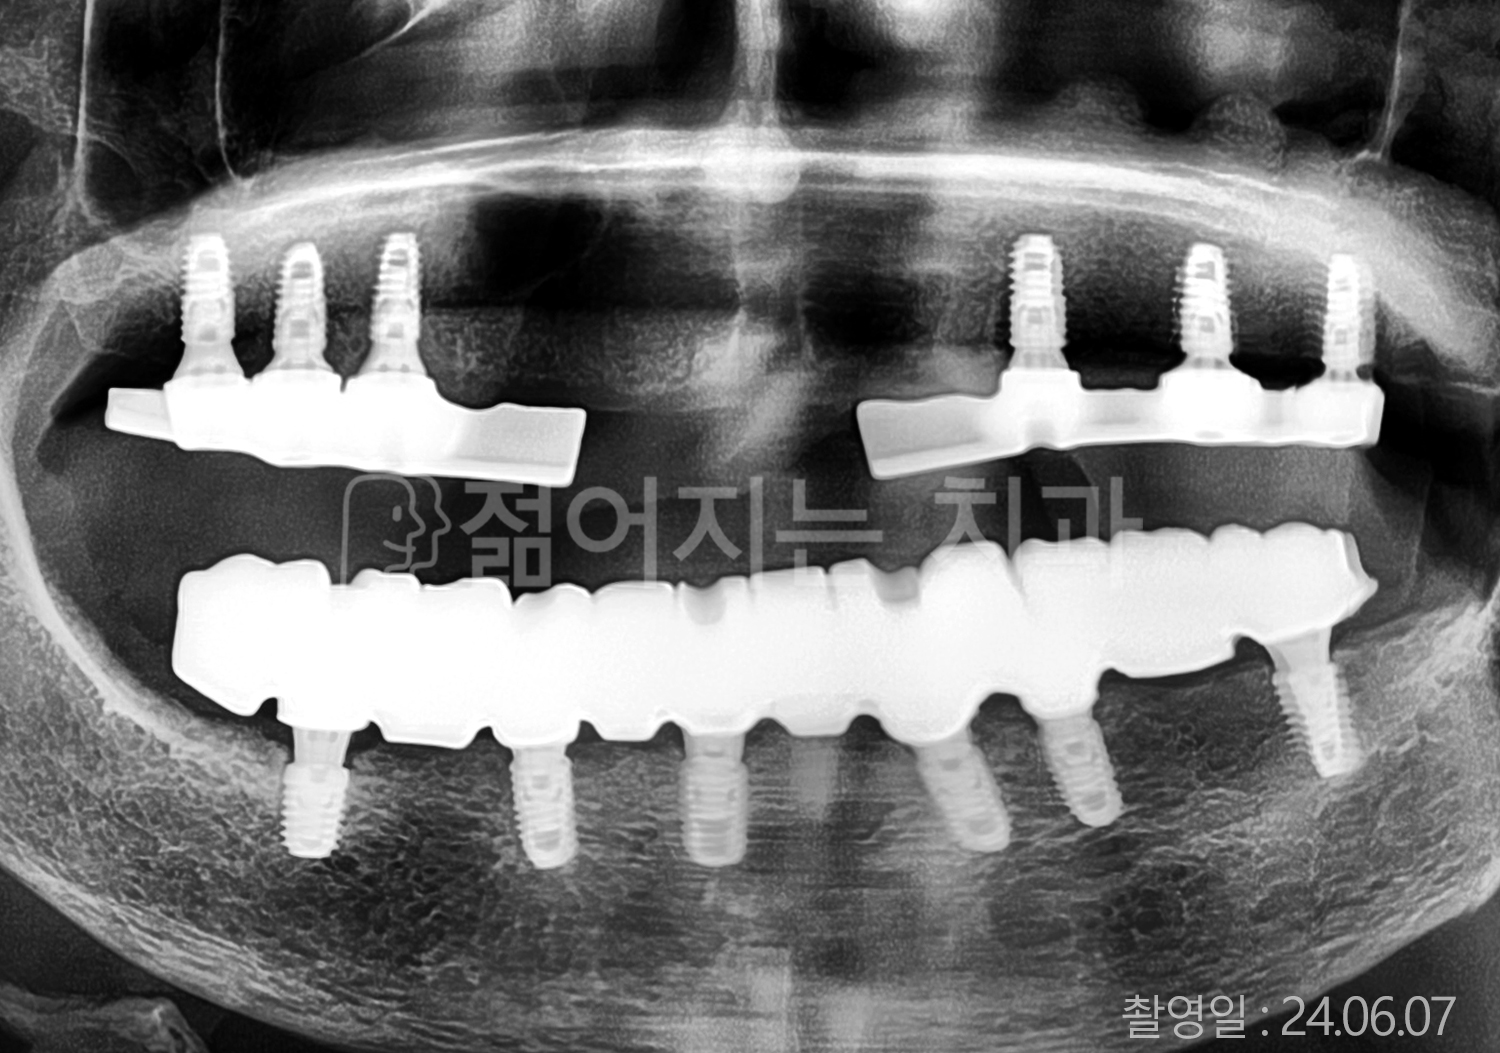

• 80대 전체치아 10개 이상 임플란트

• 60대 고혈압, 당뇨, 고지혈증 전체치아 10개 이상 임플란트

• 60대 전체치아 10개 이상 임플란트

• 60대 고혈압, 고지혈증 전체치아 10개 이상 임플란트

• 50대 고혈압, 당뇨, 고지혈증 전체치아 10개 이상 임플란트

• 70대 골다골증, 파킨스병 전체치아 10개 이상 임플란트

• 40대 전체치아 10개 이상 임플란트

• 60대 골다골증 전체치아 10개 이상 임플란트

• 40대 고혈압 전체치아 10개 이상 임플란트

• 50대 전체치아 10개 이상 임플란트

• 70대 전체치아 10개 이상 임플란트